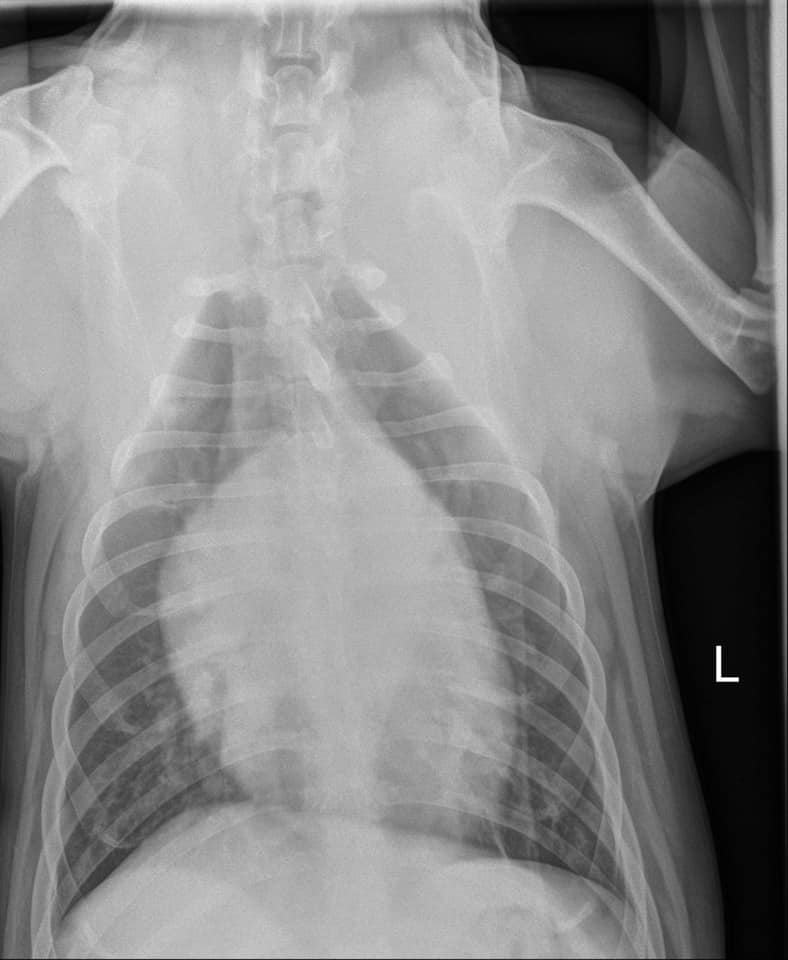

Our local veterinary hospital is seeing young dogs who should not get DCM with severely enlarged hearts. Just recently they posted radiographs of a heart that belongs to a 3-year-old Lab cross. Cardiac ultrasound confirmed the dog has dilated cardiomyopathy (DCM).

The x-rays below belong to a second young dog who has been diagnosed with DCM that day and tenth this summer alone. It is not a large hospital.

The sad part is that this is the second young dog today, and our tenth this summer to be diagnosed with DCM.

Walden Animal Hospital